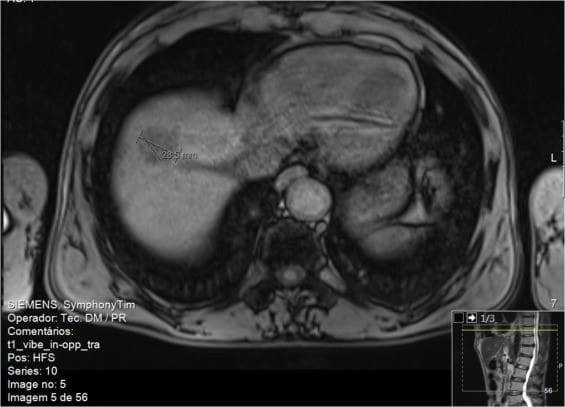

Пациент 2. Мужчина, 58 лет, с активным злоупотреблением алкоголем, курением (более 44 лет), бывший инъекционный наркоман (употреблял кокаин и героин внутривенно, в возрасте с 14 до 40 лет). ВГС (генотип 1а) был диагностирован в 2013 году. Осложнения представляли собой позднюю кожную порфирию и вторичный гемохроматоз при флеботомиях. Эластография печени показала значения фиброза печени F4 по шкале METAVIR. В 2014 году на УЗИ брюшной полости было обнаружено новообразование, которое по подозрениям представляло собой гемангиому правой доли печени. При проведении МРТ было установлено, что данное образование является лишь областью перфузионного изменения сегментов VII / VIII. В 2015 году пациент завершил 24 недельный курс лечения ледиспавиром и софосбувиром. На 24 неделе был достигнут устойчивый вирусологический ответ и исчезновением кожной порфирии. Спустя 13 месяцев после окончания лечения на магнитно-резонансной томографии был обнаружен узелок размером 29 мм в сегментах VII/VIII с подозрением на гепатоцеллюлярную карциному (рис. 2). Гистологическое исследование показало хорошо дифференцированную гепатоцеллюлярную карциному с обширными областями некроза, и признаками, указывающими на внутриопухолевую лимфо-сосудистую инвазию с отсутствием признаков сегментарной лимфо-сосудистой инвазии; минимальный хирургический запас составлял 5 мм (pT2NxR0).